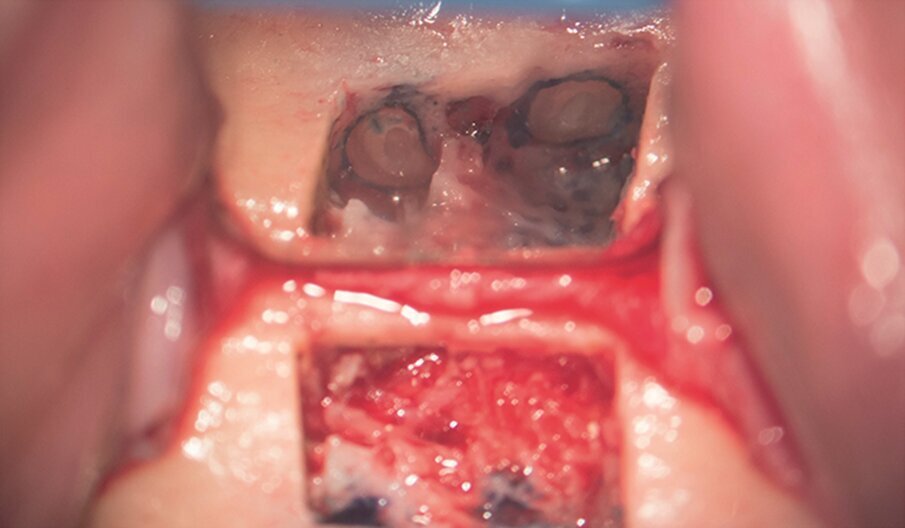

Fig. 1e–i: During microsurgery, the template was adjusted (e), …

… the limits of the cortical window were marked in the bone (f) …

… with a saw mounted in a Piezotome CUBE LED handpiece, then the bone was cut and removed (g & h) …

… to access the apical area and perform the apicectomy, apical cavity preparation and retro-filling of the mesial and distal roots (i).

Fig. 1j: Finally, the cortical window was replaced and stabilised with collagen tape.

Under local anaesthesia, a full thickness mucoperiosteal flap was reflected and the printed template was used to mark the cortical window, which was cut with a Piezotome CUBE LED handpiece (ACTEON), removed (Figs. 1e–h) and then placed in sterile saline. An apicectomy was done (Fig. 1i), and the mesial canals were retro-prepared with ultrasonic tips (NSK) and filled with EndoSequence BC RRM Fast Set Putty (Brasseler). The cortical window was then placed back and stabilized with collagen sponges in the gaps (collagen tape, Zimmer Biomet; Figs. 1j & k), and the ‑ap was sutured using 6/0 prolene suture material (Corpaul).